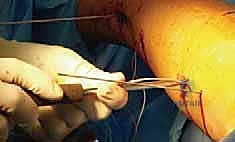

Step-by-Step Surgical Approach and Fixation Technique

Clinical & Radiographic Imaging Archive